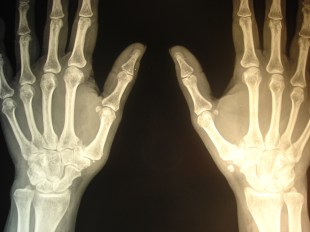

Uno de los procesos que mejor evolucionan tras la colocación de implantes de oro periarticulares es la rizartrosis del pulgar. Puede que al no ser una articulación de carga la respuesta al tratamiento sea más rápida. La degeneración articular con la pérdida de la congruencia anatómica no es un obstáculo para la recuperación funcional; la mejoría de la movilidad y la fuerza de prensión digital son notables en los casos tratados, así como la disminución-supresión del dolor. Parece cada día más evidente el relevante papel de los tejidos blandos articulares y periarticulares en la morbilidad  articular. Uno de los efectos biomédicos descritos en experimentación animal es la competencia local del oro con el calcio que se observa en las exóstosis y calcificaciones periarticulares. Se aprecia en las siguientes RX el caso de una paciente con rizartrosis de pulgar bilateral que requería una ingesta diaria de diclofenaco durante 12 años, que suspendió al día siguiente de la intervención hace unos 4 meses. Puede verse un cambio significativo en la calcificación de la mano izquierda. Es uno de los casos (bilateral) en el que el resultado funcional (movilidad y fuerza).

aspecto antes de la RX con las calcificaciones